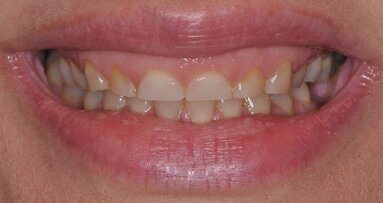

A 25-year-old woman presented to the office very interested in achieving a proper cosmetic look with a non-removable appliance. For years, she had been wearing a flipper removable replacement for her maxillary left central incisor (Fig. 1), which was traumatically lost during an accident (Fig. 2) when she was 15 yrs old. Following the accident, it was suggested by her restorative dentist (because of her young age) that she avoid a permanent splint and wait for the pulps of the adjacent teeth to mature. Years later, she was referred to me for pre-prosthetic cosmetic surgery that would allow for a non-removable, esthetically pleasing and physiologically maintainable appliance.